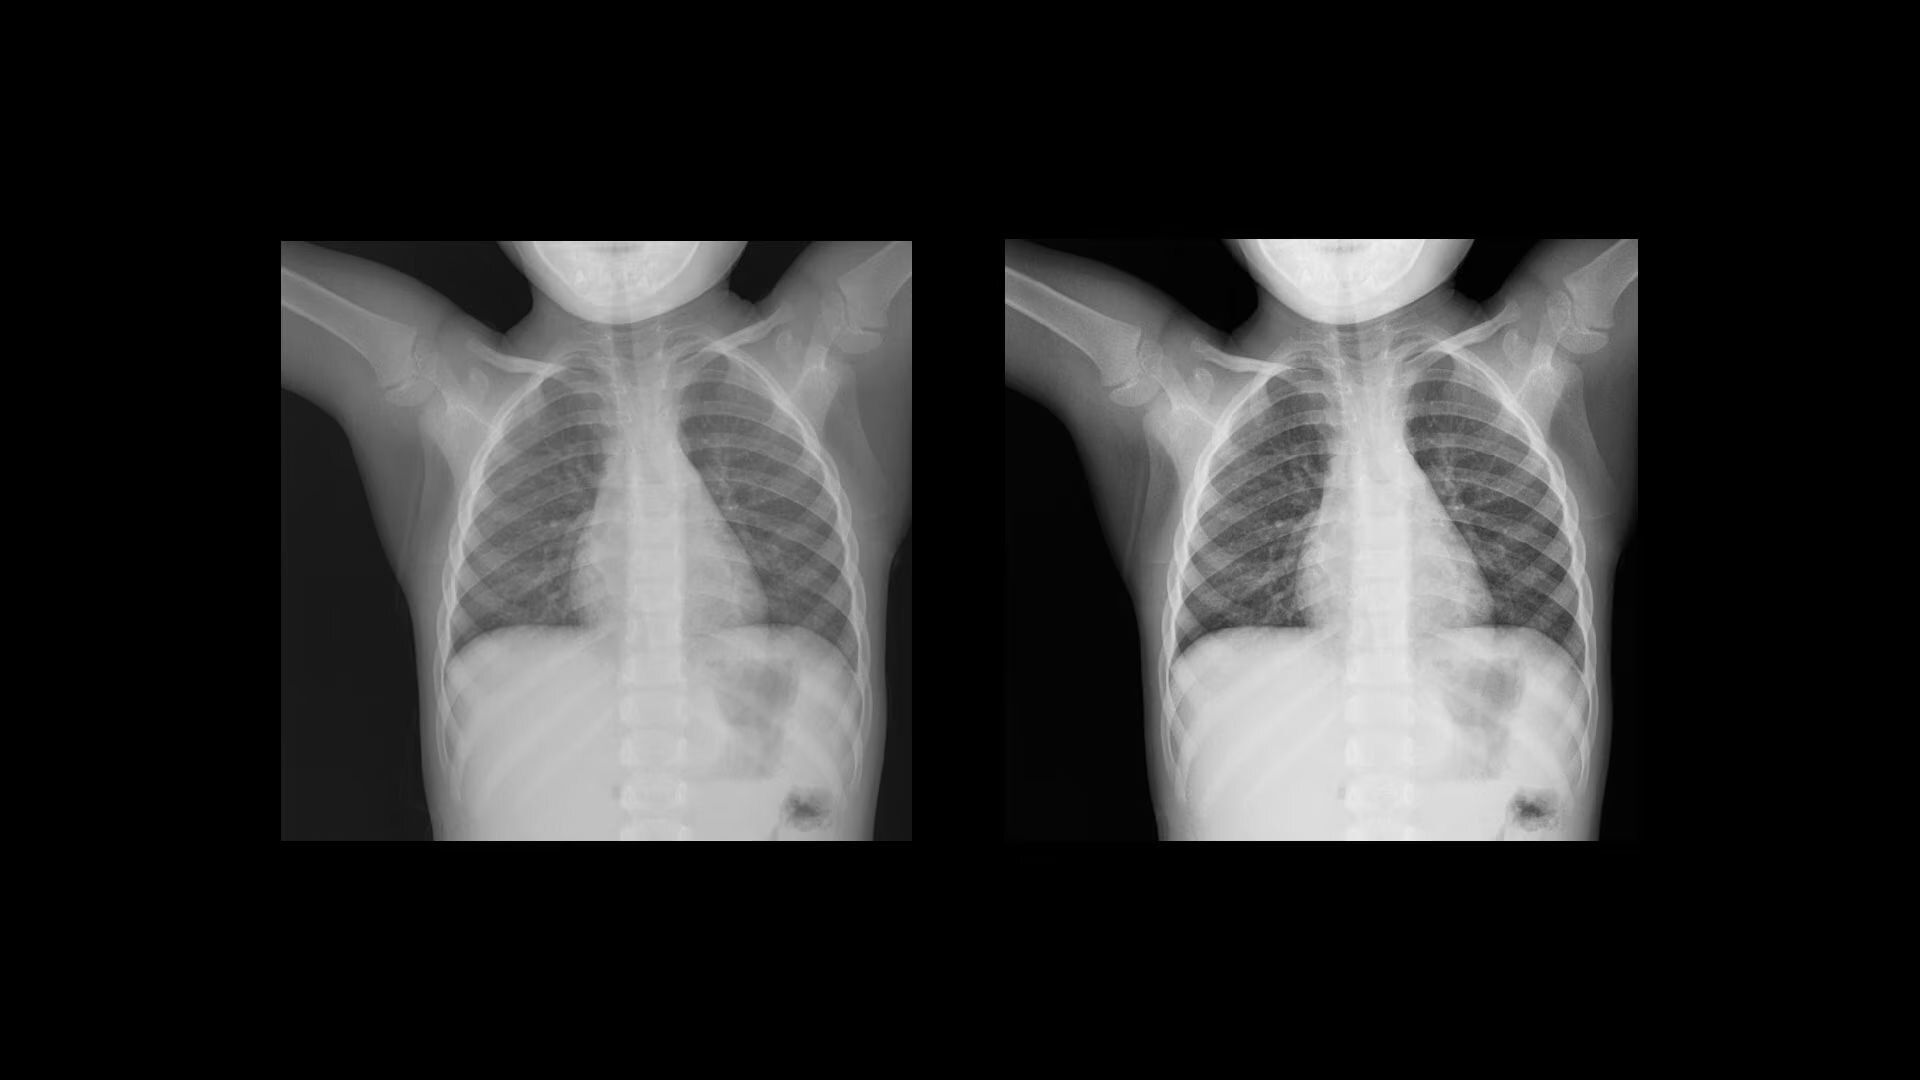

Local Contrast Enhancement (LCE) increases local contrast in both pediatric and adult chest X-ray images for better visualization of the lungs, heart, and spine regions. It is also available for ankle joint (AP), foot (AP), and patella (tangential)*, and has three levels of enhancement (low, medium and high).